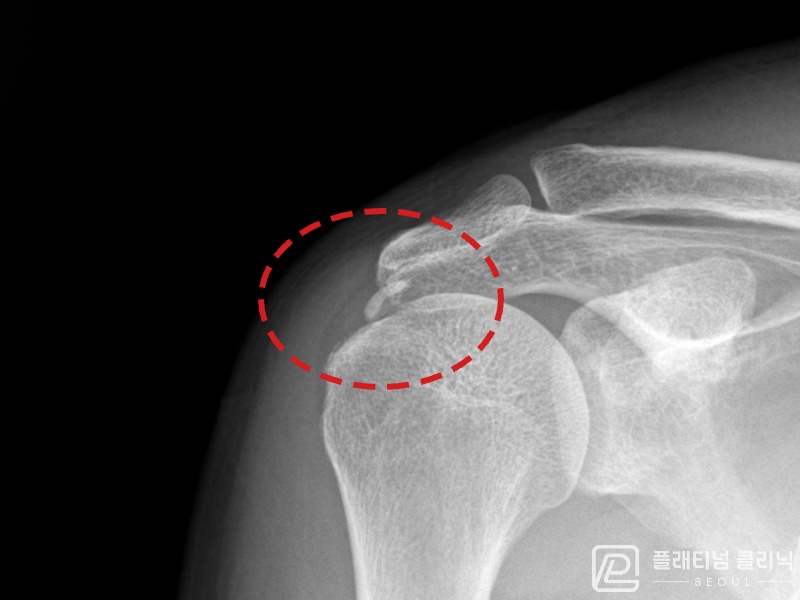

[촬영시기:21.09.02~21.10.07]

[석회분쇄흡입술] 좌측 어깨 통증으로 팔을 옆으로 올리기 어려워진 60대 남성 환자로, X-ray에서 좌측 극상근건 내 석회 침착이 확인되어 석회분쇄흡입술을 시행하였습니다.